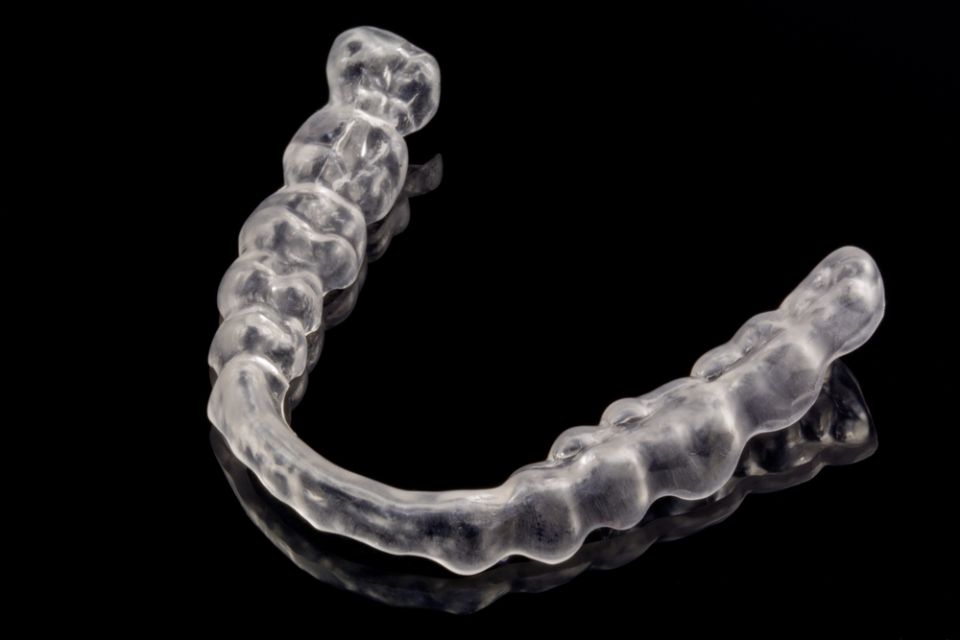

Ortodoncia

La ortodoncia es la especialidad odontológica que tiene como objetivo estudiar y corregir las malposiciones dentarias, así como las alteraciones esqueléticas de los maxilares; para resolver también problemas de prótesis o de periodoncia.

Hay diferentes opciones de ortodoncia:

. Ortodoncia con brackets estéticos o metálicos

. Ortodoncia lingual

. Invisaling®

El Invisaling es la técnica de ortodoncia en la que se emplean alineadores transparentes. La tecnología avanzada de este sistema se basa en imágenes computarizadas en 3D dónde se visualiza la imagen de los dientes desde el inicio del tratamiento hasta el resultado final. Los alienadores son totalmente personalizados.

La ortodoncia se puede realizar a cualquier edad.